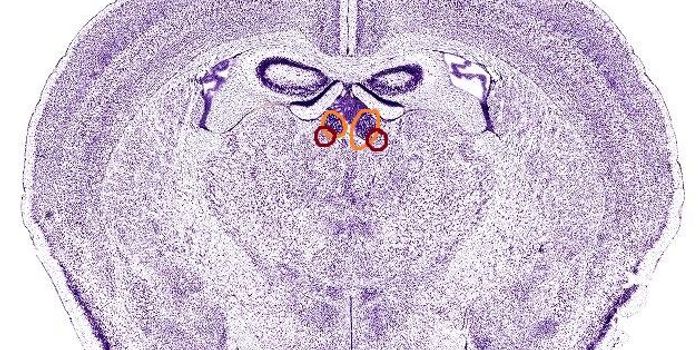

MAR 22, 2019Health & MedicinePediatric acute-onset neuropsychiatric syndrome (PANS) is a term used to describe every cause of acute-onset of obsessiv ...